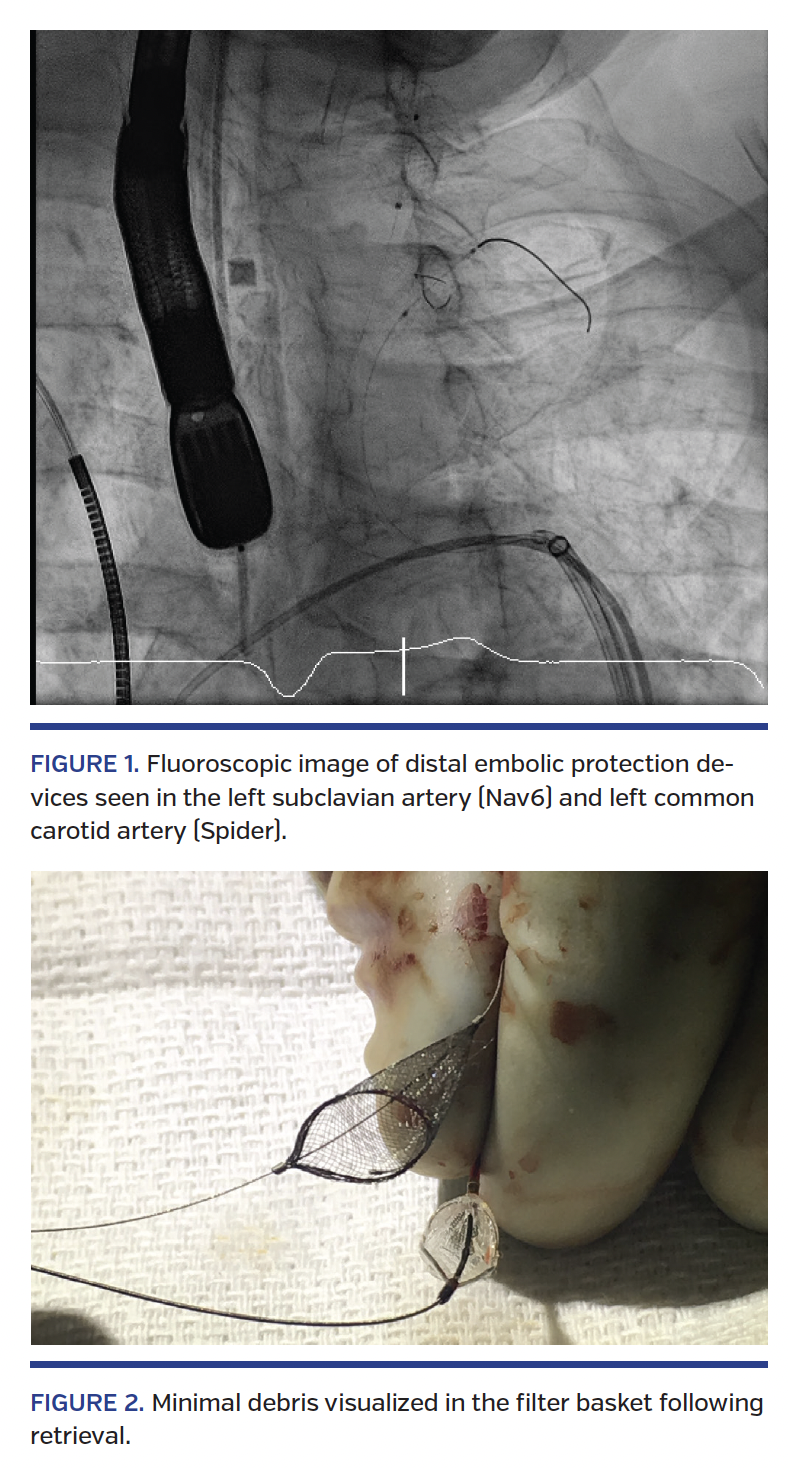

Computed tomographic angiography demonstrated a bicuspid aortic valve (Sievers type I), and confirmed heavy aortic calcification and severe bilateral iliac and left subclavian stenosis. The only option for access was the right common carotid artery (CCA). Under general anesthesia, a right CCA cutdown was performed to deliver the 34 mm Evolut R bioprosthetic valve (Medtronic). Neuromonitoring was used perioperatively. A Nav6 distal embolic protection device (Abbott Vascular) was deployed in the mid-segment of the left subclavian artery. A Spider distal embolic protection device was successfully deployed in the left common carotid artery (Figure 1). For complete protection against cerebral embolism, the distal right CCA was also clamped. At the completion of the case, both embolic protection devices were retrieved. Completion angiography of the great vessels, including the intracranials, demonstrated normal flow with no evidence of vascular injury. Postprocedure inspection of both filters revealed minor embolic debris (Figure 2). The patient awoke from general anesthesia with no neurovascular deficits and was discharged the following day without evidence of adverse clinical events.